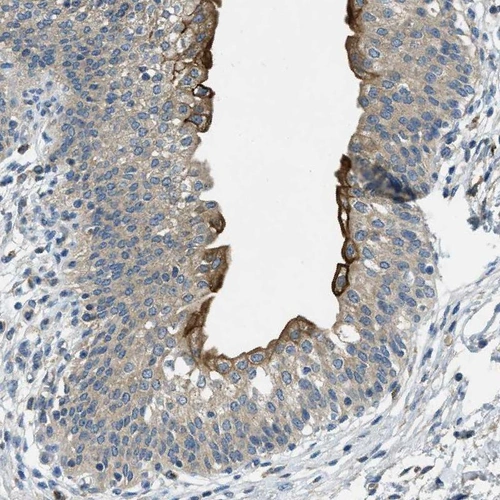

Immunohistochemical staining of human urinary bladder shows moderate to strong cytoplasmic / membranous positivity in urothelial cells.